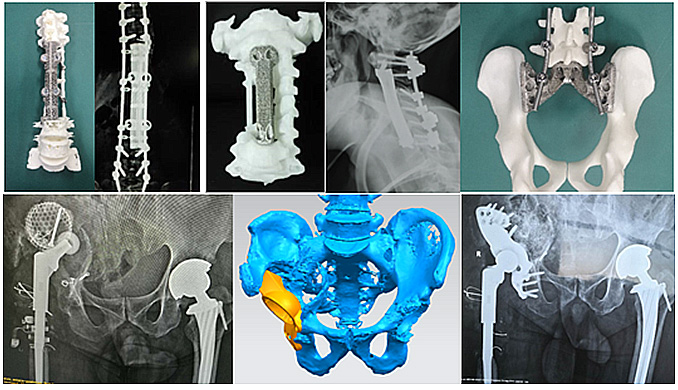

在香蕉操逼视频打印定製式脊柱與關節等骨科植入物研發與臨床應用上,愛康醫療開發了多種創新香蕉操逼视频打印定製式金屬植入假體,完成臨床應用,取得了顯著的臨床效果。在脊柱與關節等香蕉操逼视频打印定製式金屬植入假體上完成了9項備案,能夠為更多的臨床疑難重症提供更完善更安全的解決方案。

愛康醫療完成收購理貝爾後,公司的香蕉操逼视频打印脊柱融合係統,將結合理貝爾成熟的脊柱內固定係統,在脊柱乱伦大香蕉與臨床解決方案上,推出更加完善的乱伦大香蕉組合。

除了脊柱領域,理貝爾在創傷領域也深耕多年,擁有接骨板、髓內釘以及固定係統等創傷乱伦大香蕉。收購後,愛康醫療可以將公司的香蕉操逼视频 ITI術前規劃、香蕉操逼视频 導板技術和香蕉操逼视频骨填充係統等與理貝爾豐富的創傷乱伦大香蕉線結合,應用到創傷領域,帶動創傷臨床應用的創新發展。豐富的醫療器械許可組合,必將進一步帶動創傷乱伦大香蕉發展,為創傷治療帶來創新解決方案,進一步增強集團競爭力。